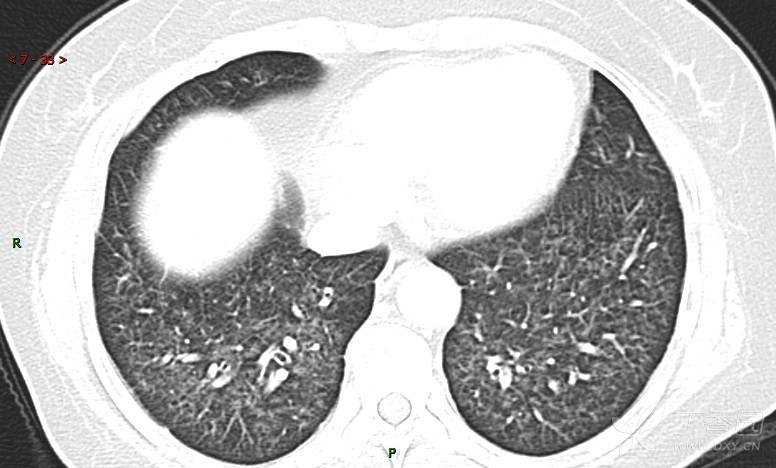

肺内弥漫性网状结节影,PET-CT却无阳性病灶,这是?(附其他2例链接)

患者活检肺组织后行PET/CT检查